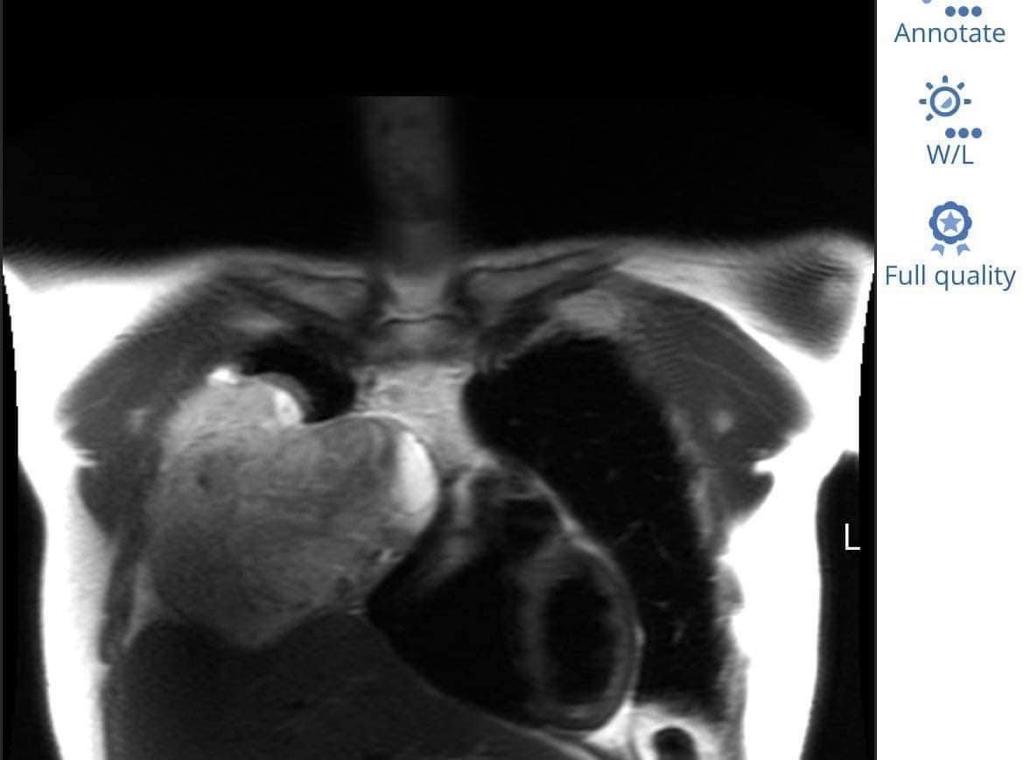

Then we see this giant tumor that’s in the shape of a mylar balloon heart.

Interviewer: What did you think when you saw your scan? Did you see anything in it?

Peter: Not initially. I just thought, “That’s really big.”

It doesn’t look real.